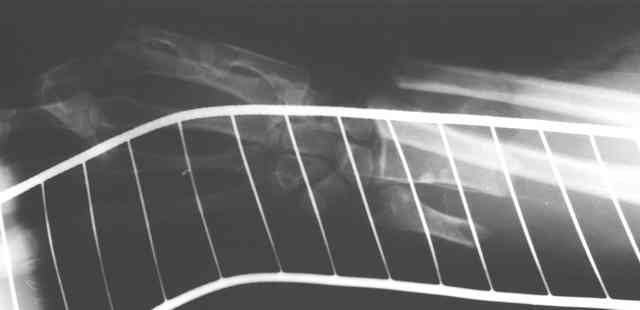

Травма 24 Октября этого года. Диагноз: Неполный травматический отрыв нижней трети предплечья. Выполнено: ПХО открытого перелома, фасциотомия, ЧКДО, шов лучевой артерии. Размозженые мышцы-сгибатели кисти и пальцев экономно иссечены - не сшивались. Спустя месяц выполнена резекция 2,5 см некротизированного конца проксимального отломка лучевой кости. На сегодняшний день по ладонной поверхности предплечья с переходом на наружний край имеется рана с дефектом мягких тканей, выполненная грануляциями с дна и с краев.

Прошу прощения - не указал, что после резекции лучевой кости рентгенобследование больной еще не проводилось. На фотогрфиях раны вертикальными черными полосами показаны границы дефекта лучевой кости.